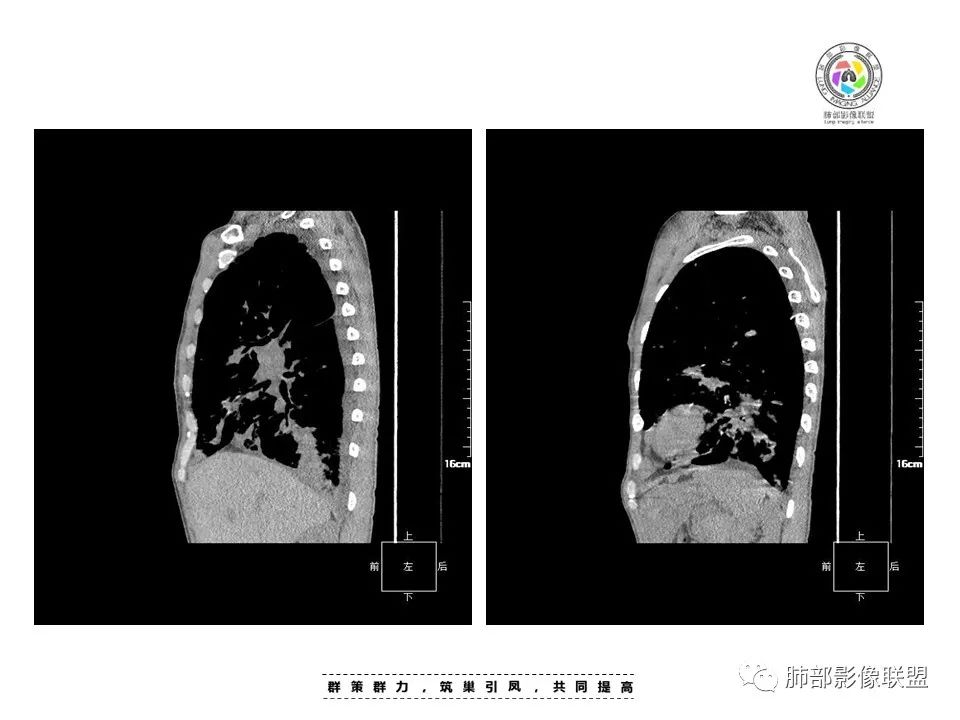

中年男性,发热、全身散在暗紫色丘疹,查CD4+T细胞64个/ul,临床信息提示AIDS并发卡波西肉瘤;CT提示双肺多发实性结节影及毛玻璃结节,部分呈点晕征,右上肺大姐姐边缘膨隆、分叶伴晕;双下肺结节沿支气管血管束分布,中轴间质增粗,部分支气管堵塞,叶间裂结节状增厚,部分结节胸膜下分布,可疑局部小叶间隔增厚,肺部病变呈淋巴分布特点,结合临床肺部病变考虑肺卡波西肉瘤,鉴别淋巴瘤。

2.本例双肺小叶间隔增厚明显,多发结节影及片状实性密度影,沿血管支气管束分布为主,两侧较为对称,病灶多环以磨玻璃晕,边界不清。

双侧胸腔少量积液。双肺门及纵隔未见明确肿大淋巴结,纵隔结构间隙模糊。

1.结节型:两肺沿支气管血管束分布的结节影,呈火焰状或星芒状、挂果征,局部周围出血磨玻璃影(肺泡出血或水肿)。

3.肺炎渗出型:

斑片渗出影,部分融合呈“火焰样”,同时有火焰样结节,小叶间隔增厚等表现。